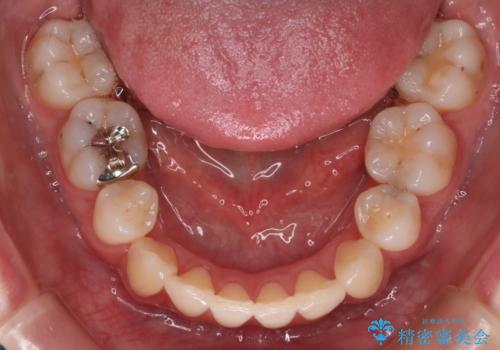

- 審美装置

- 出っぱによる口元の閉じにくさを主訴に来院されました。上顎の出っ歯と上下顎叢生も認められたため、上下顎両側4番抜歯を行い、ワイヤー矯正で治療する治療計画を立てました。

上顎にはMI(マイクロインプラント)を埋入して固定源とすることで出っ歯の改善を図りました。

少しスペースクローズに時間がかかりましたが、MIを用いたワイヤー矯正で

主訴である出っ歯と叢生が改善されました。口も閉じやすくなり、スッキリとした口元になりました。